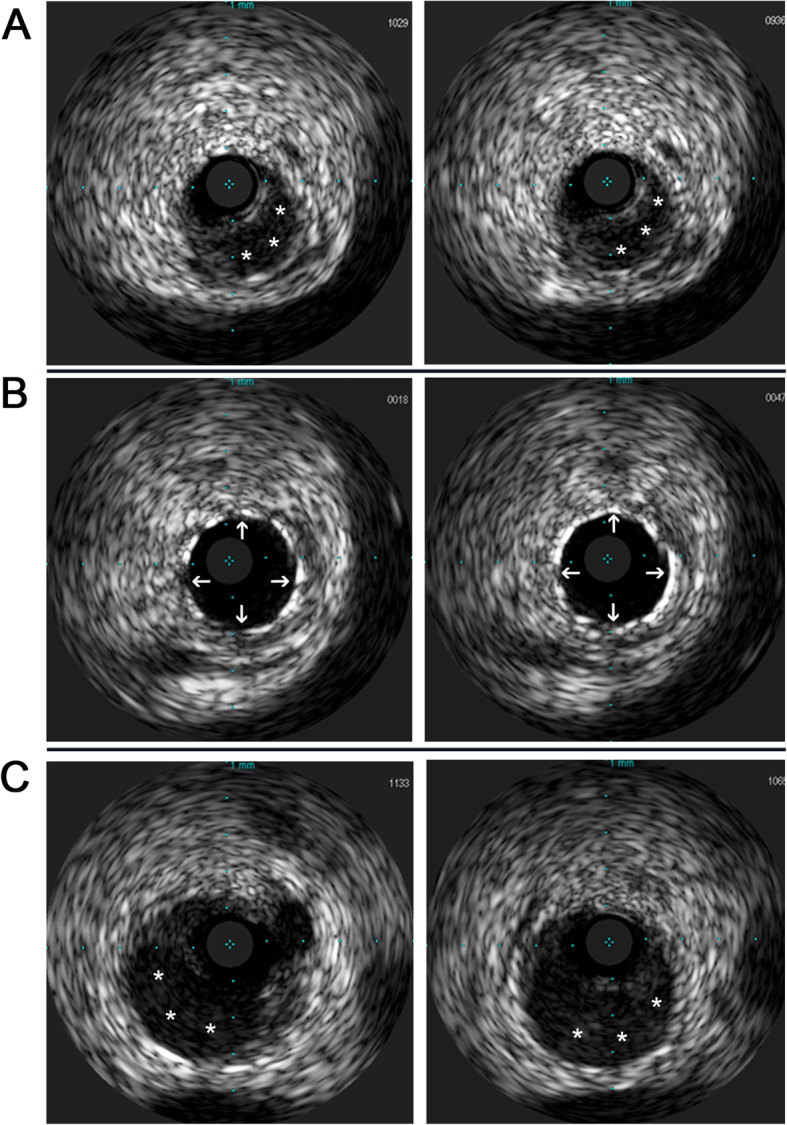

Fig. 3.

a Intravascular ultrasound (IVUS) images were presented to show the artery dissection starting from the proximal right coronary artery and ascertained the guidewire passed through the true lumen properly (left and right). b IVUS demonstrated stents attached to endothelium well and covered artery dissections completely (left and right). c IVUS showed multiple focal artery dissections located at LMC, LAD, as well as the ostium and the proximal segment of LCX (left and right). The intramural hematoma was demonstrated (*), and implanted stents were indicated with arrows